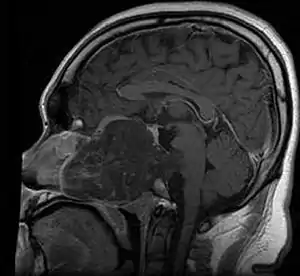

| MRI of extensive clival chordoma in 17-year-old male patient, axial view. Tumor in the nasopharynx extending from nasal cavity to brainstem posteriorly is clearly visible. | |